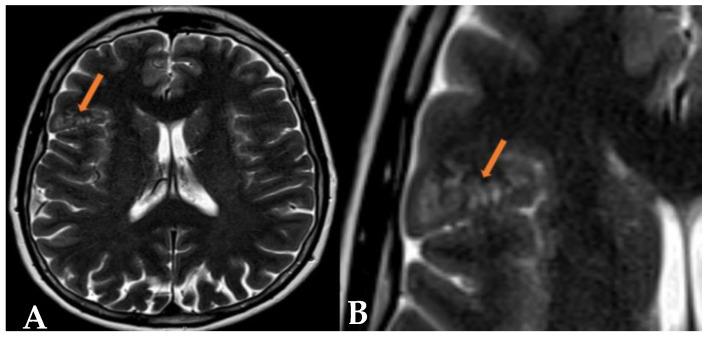

Multinodular Vacuolating Neuronal Tumors (MVNTs) are mixed glial-neuronal brain lesions classified as World Health Organization (WHO) CNS grade 1 tumors, often associated with long-term epilepsy. First described by Huse et al. in 2013 and included in the WHO CNS classification in 2016, MVNTs present a range of clinical manifestations, from symptomatic to asymptomatic. They typically affect young to middle-aged adults and exhibit diverse presentations. Radiologically, MVNTs are usually supratentorial, frequently located in the temporal lobe but also observed in the frontal and parietal lobes. MRI is essential for diagnosis, revealing multiple coalescing subcortical or cortical nodules with hyperintense signals on T2-weighted/FLAIR sequences, often without peripheral edema or mass effects. This paper presents two cases: one symptomatic MVNT with significant clinical manifestations, and the other documenting an incidental finding of MVNT in an asymptomatic patient. One case shows typical temporal lobe localization, while the other highlights a rare frontal lobe localization, with clear radiological findings on T2/FLAIR sequences. These cases illustrate the varied clinical presentations of MVNTs and emphasize MRI's critical role in diagnosis and management. Asymptomatic cases often require conservative management, stressing the avoidance of unnecessary invasive procedures and the importance of regular monitoring.

多结节空泡状神经元肿瘤(MVNTs)是一种神经胶质-神经元混合性脑病变,被归类为世界卫生组织(WHO)中枢神经系统1级肿瘤,常与长期癫痫相关。MVNTs于2013年由胡斯等人首次描述,并于2016年被纳入WHO中枢神经系统分类,其临床表现多样,从有症状到无症状。它们通常影响年轻至中年成年人,表现形式多样。在影像学上,MVNTs通常位于幕上,常位于颞叶,但也可见于额叶和顶叶。磁共振成像(MRI)对诊断至关重要,显示在T2加权/液体衰减反转恢复(FLAIR)序列上有多个融合的皮质下或皮质结节,信号增强,通常无周围水肿或占位效应。本文介绍了两例病例:一例是有明显临床表现的有症状MVNT,另一例记录了在一名无症状患者中偶然发现的MVNT。一例显示典型的颞叶定位,另一例突出了罕见的额叶定位,在T2/FLAIR序列上有明确的影像学表现。这些病例说明了MVNTs的不同临床表现,并强调了MRI在诊断和管理中的关键作用。无症状病例通常需要保守治疗,强调避免不必要的侵入性手术以及定期监测的重要性。